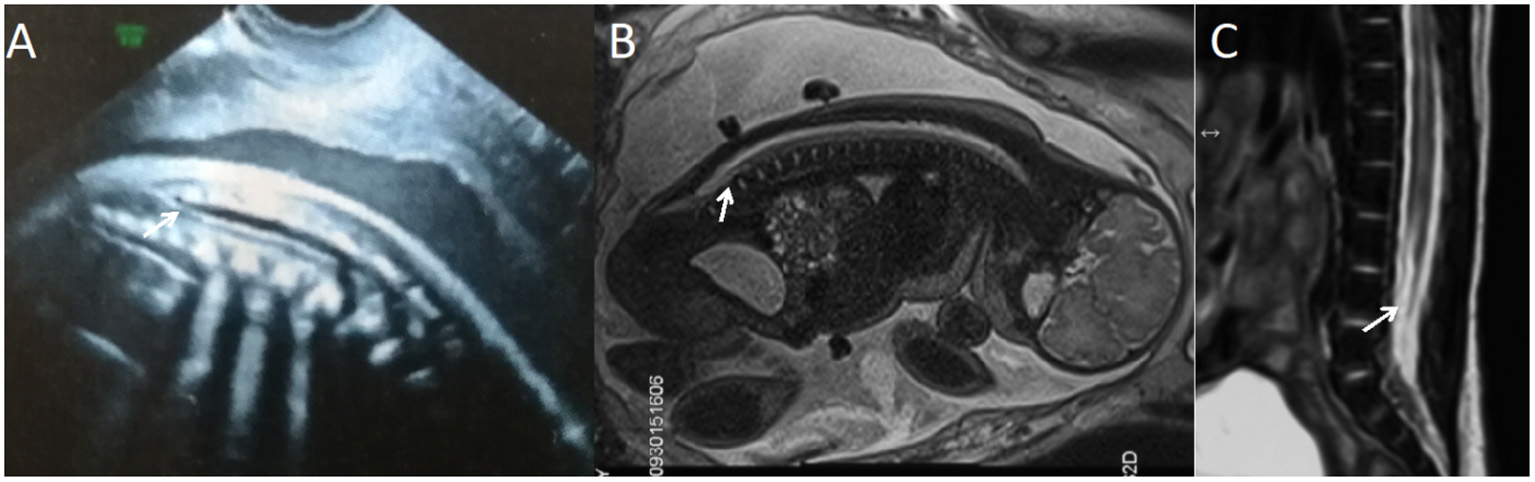

Figure 3

A fetus with simple spinal tethered cord syndrome. (A) The prenatal ultrasound examination at 20 + 5 weeks of gestation showed the lower conus medullaris. (B) Fetal magnetic resonance imaging (MRI) examination at 20 + 6 weeks of gestation showed the lower conus medullaris. (C) T2 sagittal MRI of the lumbosacral vertebrae 22 days after birth suggested simple spinal tethered cord syndrome.